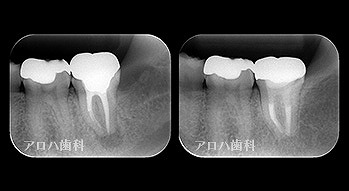

透過像が消失したケース

case1

初回根管治療

1年予後

治療回数1回